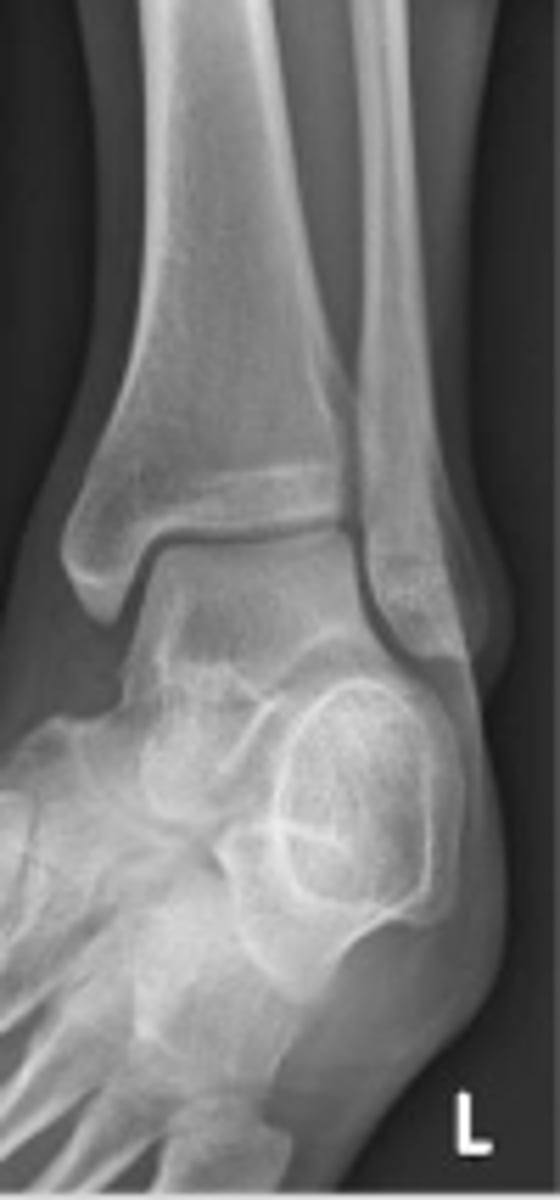

Left internal oblique ankle

What is the name of the radiographic view?